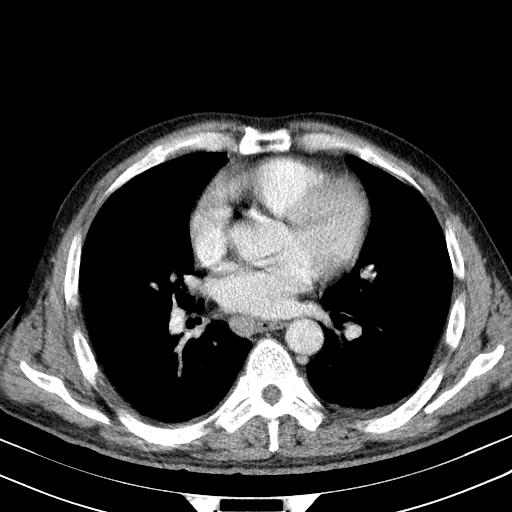

先行ct平扫,纵膈内多发软组织影,ct值约为36hu,以下为增强扫描和腹部平扫。

经典?纵膈多发肿大淋巴结。腹膜后未见异常。

淋巴瘤?胸腺瘤?

1)考虑淋巴瘤。2)双侧少量胸腔积液。